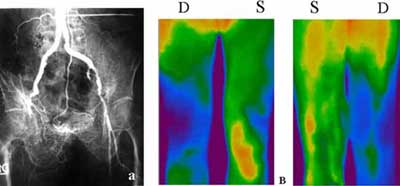

Термографическая картина в указанных группах больных оказалась весьма различной. У 4 пациентов с тромбозированной подвздошной и бедренной артериями, но проходимыми обеими артериями голени, гипотермическая зона начиналась еще в верхней половине бедра, постепенно спускаясь в дистальном направлении и сохраняя равномерный характер в обеих проекциях без значимого термоградиента (Рис. 1). Подобная картина наблюдалась и в 8 случаях с облитерацией бедренной артерии, с той разницей, что гипертермия начиналась в средней трети бедра, а «теплые» поля достигали нижней трети голени в полном соответствии с показателями регионального систолического давления в периферических артериальных магистралях (Рис. 2).

Рис. 1. Облитерирующий атеросклероз (а) Ангиография. Обтурация правой подвздошной артерии. (б) Выраженная гипотермия бедра и правой голени в обеих проекциях.

Рис. 2. Облитерирующий атеросклероз. (а) Ангиография. Облитерация нижней половины правой бедренной артерии. Берцовые артерии проходимы. (б) Выраженная гипотермия правой голени равномерно в обеих проекциях.